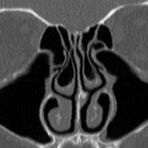

• Nasennebenhöhlen (Entzündungen, Tumore)

Kopf